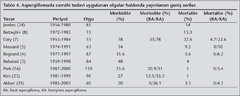

Kesin tedavinin cerrahi rezeksiyon oldu?u geni? serili yaz?larda da belirtilmekte, ancak %1-22 aras?nda mortalite ile %23-78 aras?nda morbidite olabilece?i g?z ?n?ne al?narak cerrahi rezeksiyon ?ncesi iyi d???n?lmesi ve yeterli pulmoner fonksiyonlara sahip olan hastalara rezeksiyon planlanmas? ?nerilmektedir (3,4,7,8,16,23,24). Mortalite s?kl?kla kronik solunum yetmezli?i veya pn?moniye ba?l? oldu?u i?in altta yatan pulmoner durum en ?nemli fakt?rd?r. Bu da kompleks aspergillomal? olgularda daha fazla mortaliteyi a??klamaktad?r. Cerrahi mortalitemiz son y?llardaki literat?rlerle uyumlu olarak %5.6 idi. Son yay?nlarda mortalite ve morbiditenin azald??? g?r?lmektedir (Tablo 4) (4,16,23). Bu hem olgular?n dikkatli se?ilmesine hem de cerrahi tekniklerin ilerlemesine ba?lanabilir. Ayr?ca, kompleks olgularda mortalite ve morbiditenin basit aspergillomaya g?re daha fazla olu?tu?unun belirtilmesi ve de son y?llardaki yay?nlarda? basit aspergillomal? olgu say?s?n?n artmas? bu d??meyi a??klayabilir (4,7,16,25) (Tablo 4). Yara yeri infeksiyonu gibi min?r komplikasyonlar g?r?lebilece?i gibi hemoraji, ampiyem, ekspansiyon kusuru, BPF gibi maj?r komplikasyonlar da g?r?lebilmektedir (3,4). Olgular?n %57.7'sinde morbidite geli?ti?ini g?rd?k. En s?k saptanan komplikasyonlar literat?rle uyumlu olarak uzam?? hava ka?a??, ekspansiyon kusuru ve ampiyemdi. Yay?nlarda belirtilen hemoraji komplikasyonunun bizim serimizde olmamas?n? ekstraplevral diseksiyonu ?ok uygulamam?za ba?lamaktay?z. Komplikasyon geli?en olgular?n istatistiksel olarak kompleks olgularda daha fazla oldu?unu saptad?k. Basit aspergillomal? olgular?n s?kl?kla altta yatan bir hastal?k olmadan aspergilloma hastal???na yakaland?klar? ve de bu olgulara parankim koruyucu cerrahinin istatistiksel olarak daha fazla uygulanmas? da basit aspergillomal? olgularda daha az komplikasyon izlenmesini a??klayabilir. Son y?llarda basit aspergillomal? olgular?n artt??? g?z ?n?ne al?n?rsa olgu say?s?n?n artmas?yla komplikasyon oran?n?n azalaca?? iddia edilebilir.

Be? y?ll?k sa?kal?m %80-90 aras?ndad?r (3,23). ?al??mam?zda ?? y?ll?k sa?kal?m %90'd?r. Literat?rle uyumlu olarak (7,23,25); kompleks olan grubun basit olan gruba g?re uzun s?reli sa?kal?m?n?n istatistiksel olarak anlaml? olmasa da daha k?t? oldu?u saptand?.